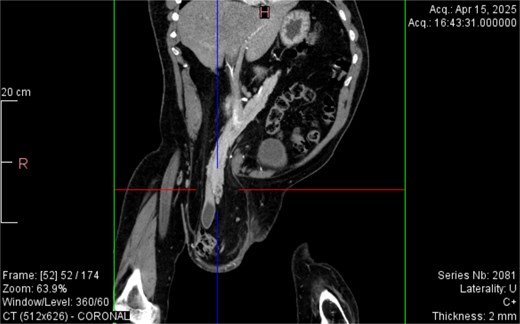

CT imaging (Figs 2–5) revealed a right inguinal hernia containing small bowel loops, ascending colon, the second and third portions of the duodenum, and the pancreatic head. The pancreatic head appeared rotated and displaced inferiorly into the hernia sac, without signs of acute pancreatitis.

Coronal CT view inguinal hernial sac with pancreatic head and D2 and D3 segment of duodenum.

Additionally, incidental findings (Fig. 2) included multiple calculi within the left hepatic duct. Though the patient was asymptomatic from a hepatobiliary standpoint, the presence of these stones raised concern for potential biliary stasis.